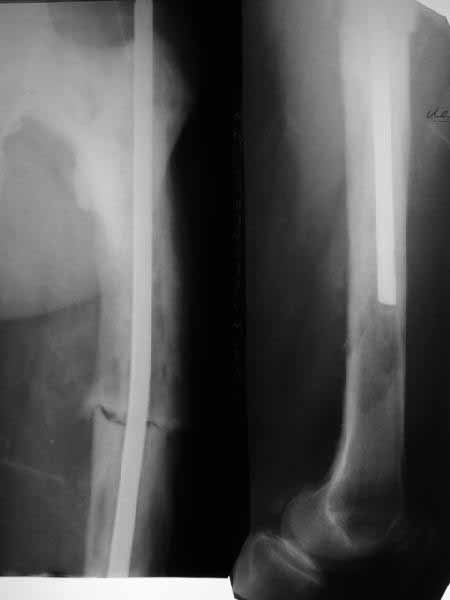

THX to all colleagues for their opinions. Chest xrays are clear. Our radiologists explored films and swear the bone changes are Paget's. Finally we proceeded with a minimal plan - the existed nail was pulled out (quite easily). It turned out that a largest available nail was only 11 mm 40 cm, so i inserted it and locked dynamically. The procedure was quick. As immediate effect the patient marked lack of clicking which disturbing him before. We plan to discharge him ASAP with recommendations of biphosphonates etc.

It looks like Paget's disease to me. The original nail is small, short and unlocked. Make the second one reamed, large (14 mm), long (past the distal lucency) and statically locked for rotational control. Send tissue for pathology.